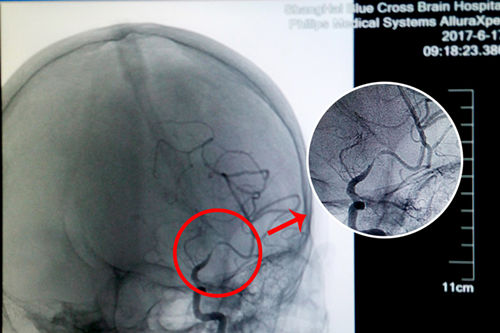

由于術(shù)前DSA檢查得知盛阿姨的血管狹窄程度超過70%,球囊擴(kuò)張支架置入手術(shù)存在較大的難度和風(fēng)險,但這并沒有難住李振并主任,他認(rèn)為努力爭取挽救患者生命的寶貴時機(jī)更為重要。經(jīng)過一系列詳細(xì)周全的術(shù)前準(zhǔn)備,李主任和同事們開始了手術(shù)。

站在手術(shù)臺前的李主任,表現(xiàn)出的是與平日不同的冷靜和沉著。經(jīng)術(shù)中精準(zhǔn)測量發(fā)現(xiàn),患者盛阿姨血管狹窄達(dá)到了77%,血管非常狹窄,使放置球囊擴(kuò)張支架的難度更大。好在李主任積累了豐富的DSA手術(shù)經(jīng)驗(yàn),經(jīng)過仔細(xì)小心的操作,導(dǎo)絲成功地通過了狹窄的血管。李主任用他的“血管藝術(shù)”使瀕臨枯萎的血管重新綻放出了生命的活力,最終原本非常狹窄的血管腔順利張開了:“……將球囊擴(kuò)張支架置入狹窄處,觀察后準(zhǔn)確釋放球囊擴(kuò)張支架,再造行3D造影,顯示血管擴(kuò)張,血流恢復(fù)正常。(摘自術(shù)后小結(jié))”。

術(shù)前DSA影像顯示,患者大腦中動脈血管70%以上狹窄